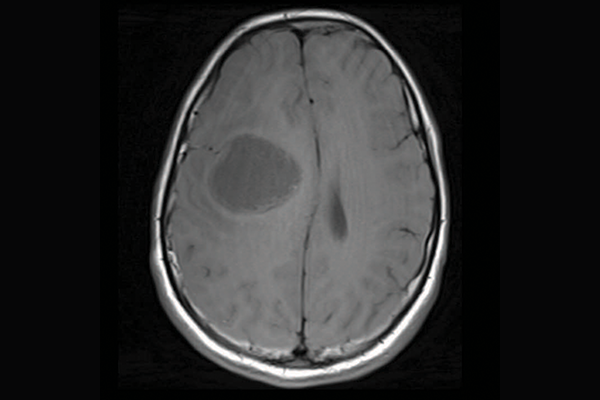

Brain scans showing three different subtypes of priMMRD high-grade glioma.

A scan of a brain with priMMRD subtype 1

priMMRD-1: The ultra hypermutant

These tumours are the most common, with 62 per cent of tumours having both MMRD mutations and polymerase proofreading deficiency (PPD), making them extremely sensitive to immunotherapy. A first-in-kind clinical trial called U-R-Immune Glioma, led by Drs. Eric Bouffet and Das at SickKids, is already pursuing an immunotherapy-first approach for these patients, sparing initial radiation therapy.